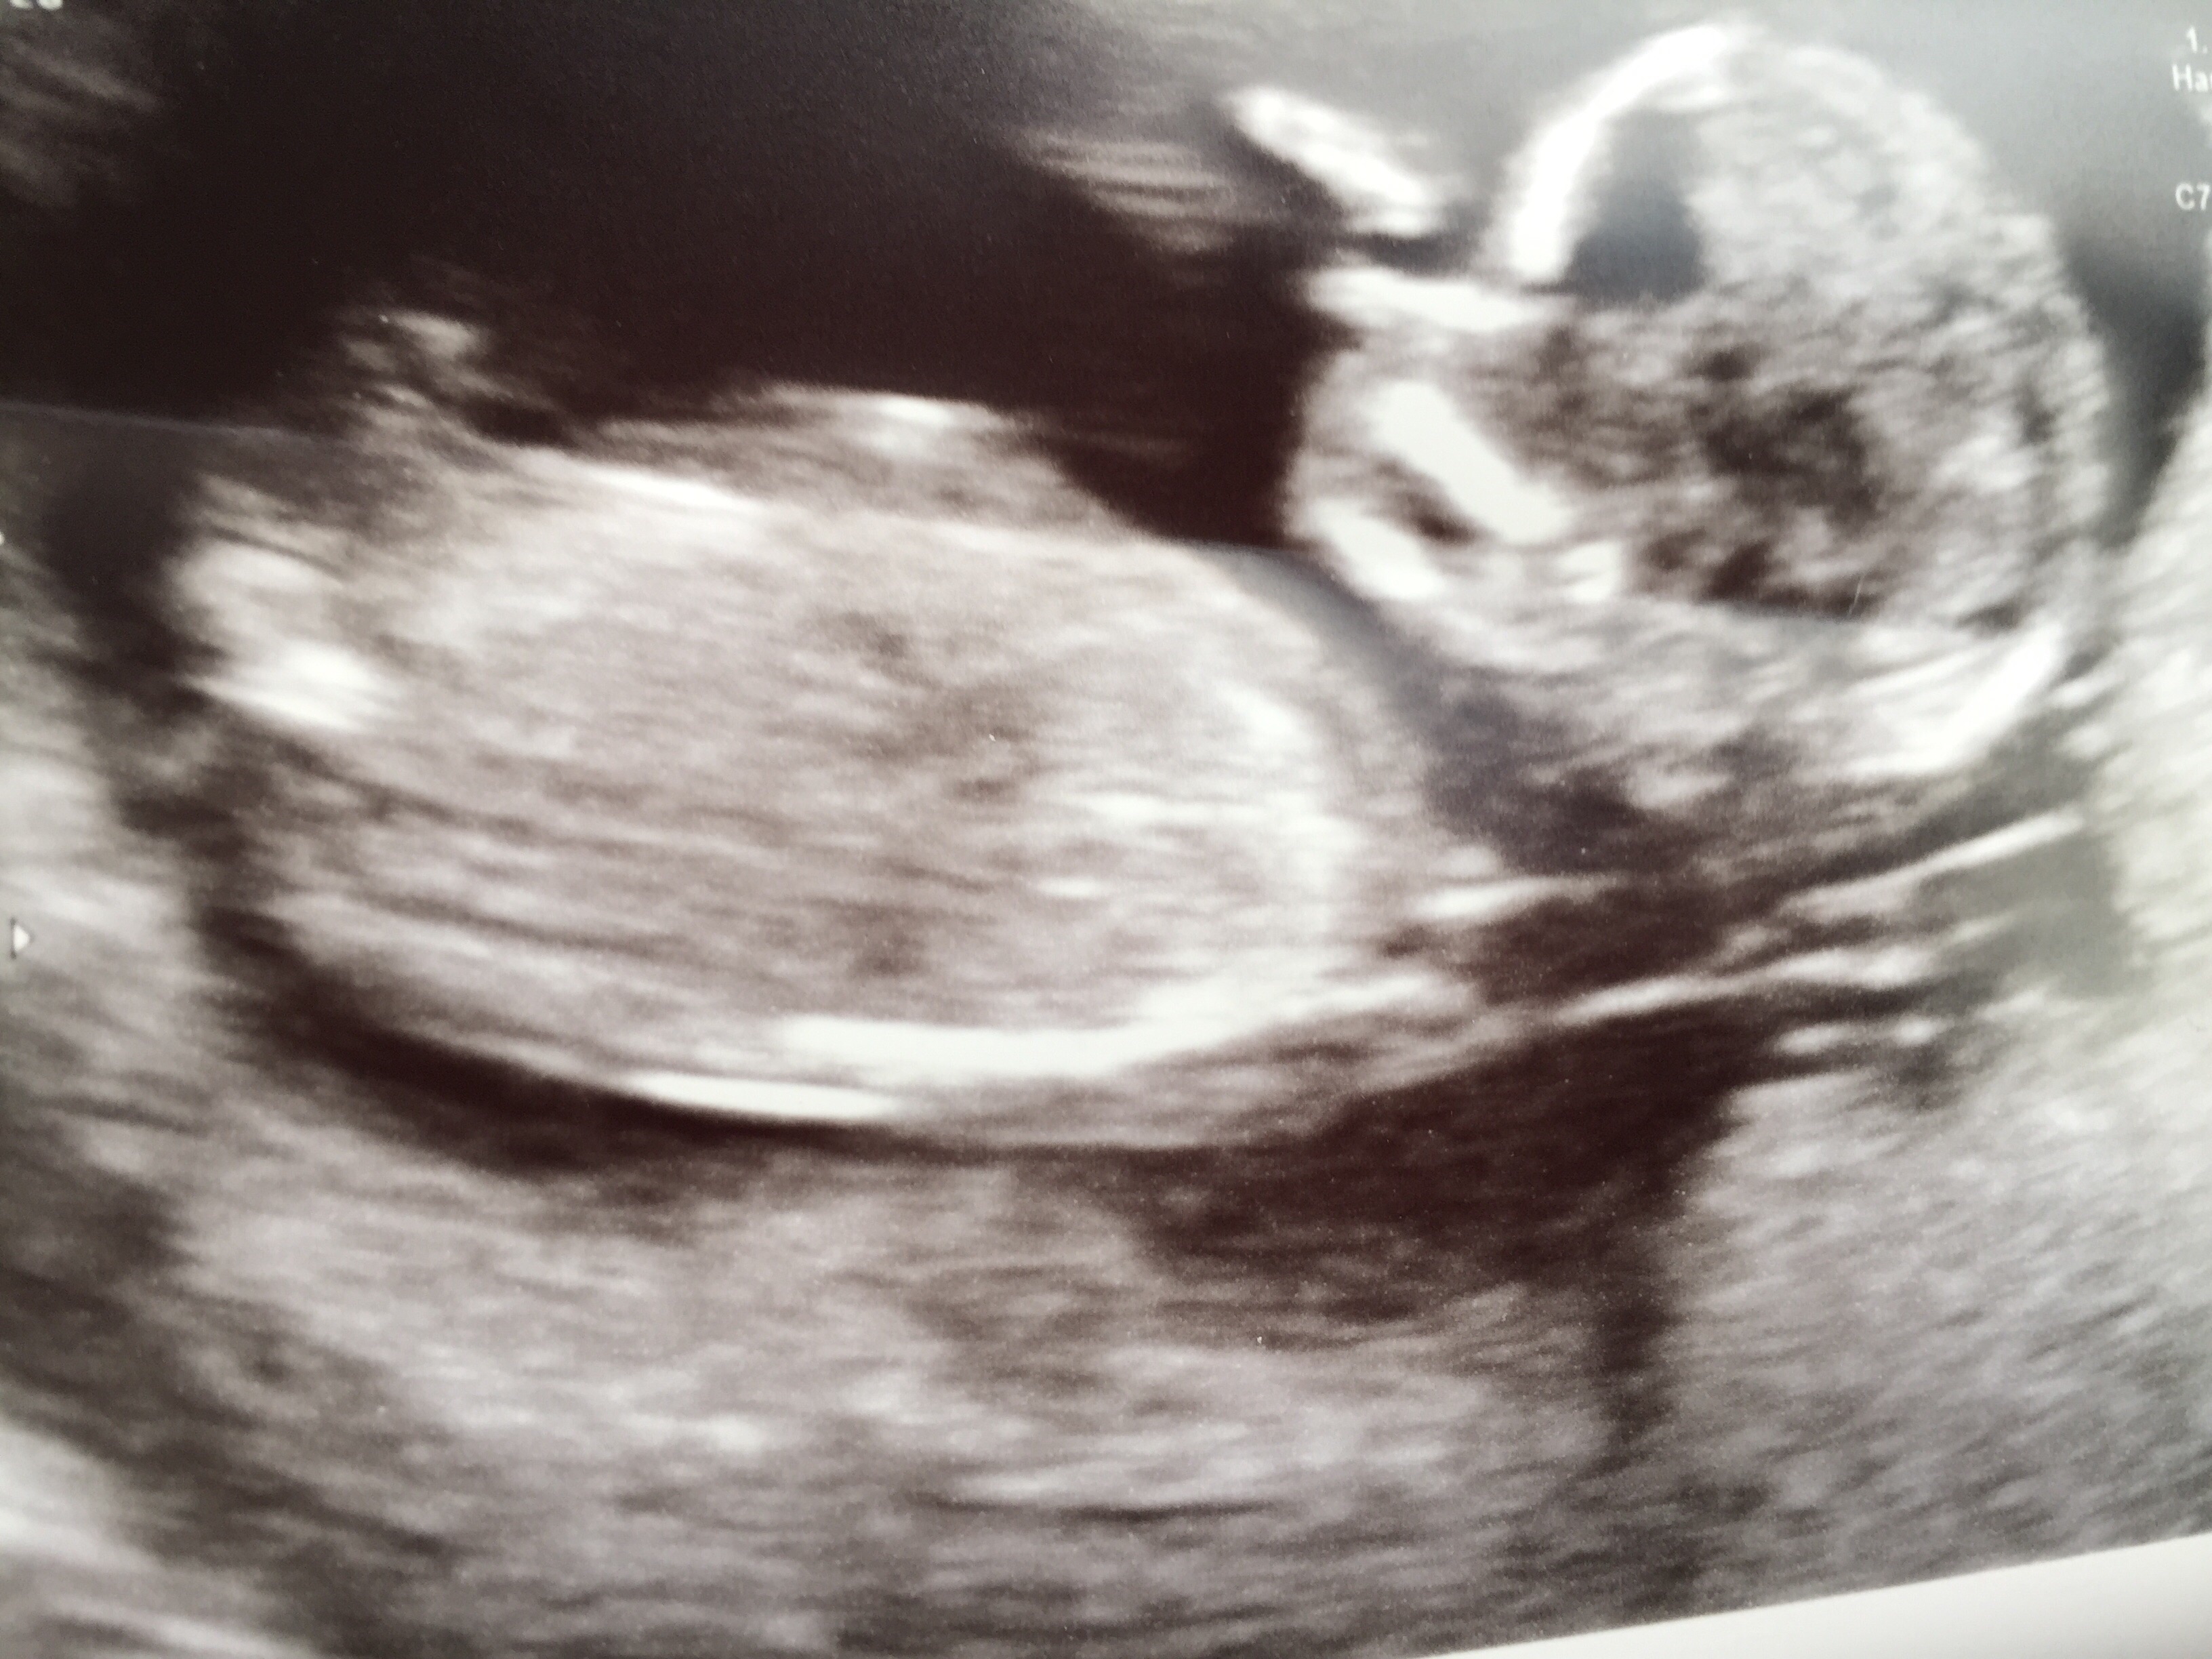

Lol, interesting as the high risk OB who's and ultrasound specialist told us 95% girl! We will see I guess!

Looking like a boy.

The first post I was thinking girl, but the fourth post really does look boy. I would generally trust a tech though!